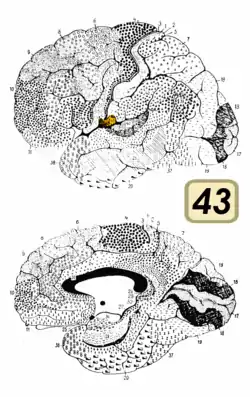

Brodmann area 43

Brodmann area 43, the subcentral area, is a structurally distinct area of the cerebral cortex defined on the basis of cytoarchitecture. Along with Brodmann Area 1, 2, and 3, Brodmann area 43 is a subdivision of the postcentral region of the brain,[1] suggesting a somatosensory ('feeling of the body') function. The histological structure of Area 43 was initially described by Korbinian Brodmann, but it was not labeled on his map of cortical areas.[2]

In the human subcentral area 43, a sub area of the cytoarchitecture is defined in the postcentral region of the cerebral cortex. It occupies the postcentral gyrus, which is between the ventrolateral extreme of the central sulcus and the depth of the lateral sulcus, at the insula. Its rostral and caudal borders are approximated by the anterior subcentral sulcus and the posterior subcentral sulcus, respectively. Cytoarchitecturally, it is bounded rostrally, by the agranular frontal area 6, and caudally, for the most part, by the caudal postcentral area 2 and the supramarginal area 40.[1]